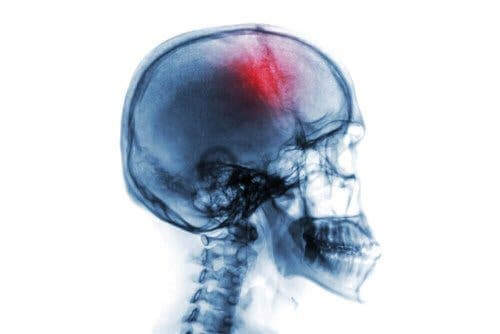

السكتة الدماغية هي متلازمة عصبية مفاجئة وحادة تظهر بسبب العديد من عوامل الخطر، وتؤدي إلى العديد من الأعراض التي لا يجب تجاهلها أبدًا. وهي تشمل نزيفًأ أو نقصًا في تدفق الدم إلى الدماغ.

تشير السكتة الدماغية إلى خلل في تدفق الدم إلى المخ. قد يحدث ذلك بسبب انسداد في أي من الأوعية الدموية التي تغذي الدماغ أو بسبب نزف داخل الدماغ.